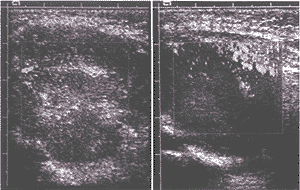

中国超声医学杂志990729 患者女性,6个月,生后父母发现右小腿近端有一肿物,近来逐步增大而来就诊。临床 检查:肿物质中等,无活动。彩色多普勒超声所见:右小腿肿物处探查可见 大小约5.7cm×3.8cm×5.1cm的混合性肿物,边界尚清,其中间回声较强,周围为低回声 所包绕,肿块内血流丰富(图1左),测其血流为高速低阻血流,阻力指数RI=0.40,CDE: 其内还有丰富的低速血流(图1右)。超声诊断:右小腿恶性肿物。手术所见:右小腿外侧可 见大 小6cm×4cm×5cm的椭圆形包块,包块呈淡红色、鱼肉状,质地中等,包膜完整,未侵及周 围软组织和骨骼。病理诊断:平滑肌肉瘤。

左图:CDFI所见 右图:CDE所见

图1 平滑肌肉瘤